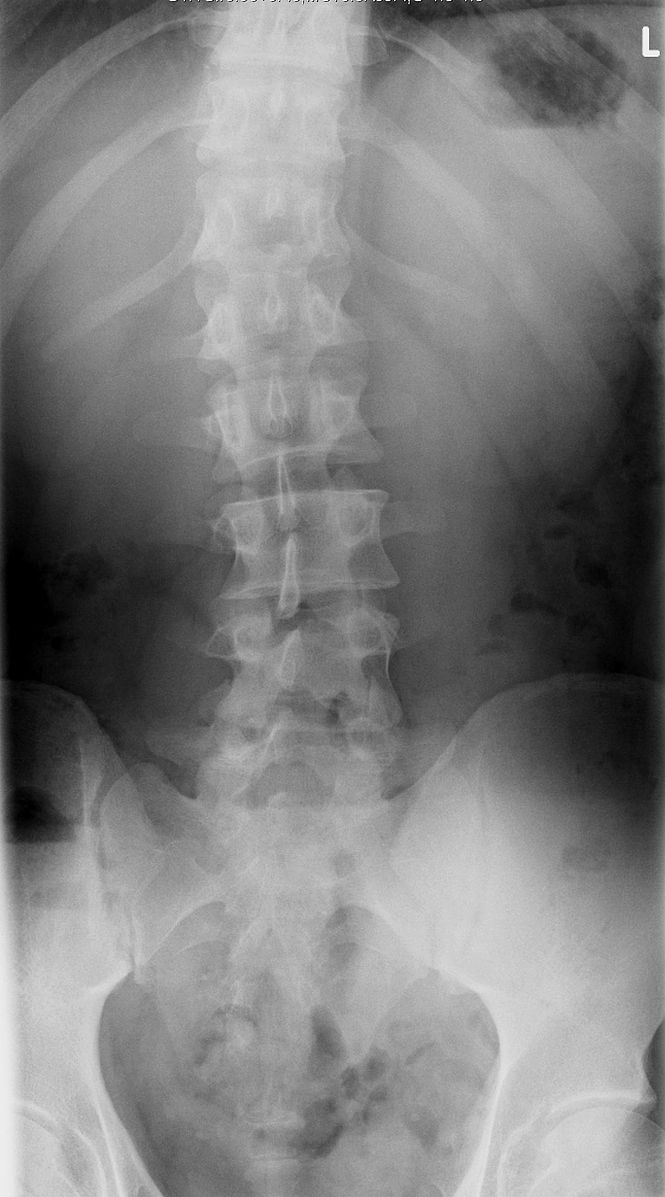

Scoliosis

Scoliosis refers to lateral deviations in the vertebral column, which can be caused by erosion of vertebrae, muscle weakness, or uneven growth.